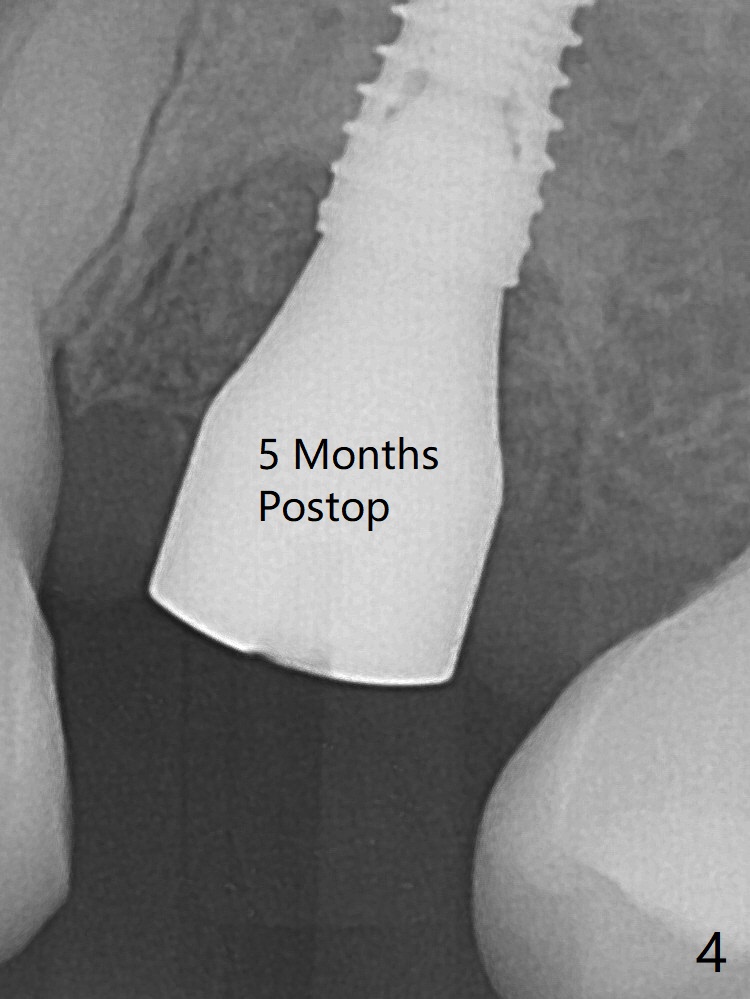

When a 2x16 mm parallel pin is inserted at #13 after extraction, PA does not show the upper end, as related to the long bone (Fig.1). In spite of underprep osteotomy, a 3.8x18 mm implant achieves ~ 20 Ncm of insertion torque (Fig.2). The long implant is still in the lower half of the triangular (cone-shaped) bone (Fig.3 red dashed line) between the nasal cavity (N) and the maxillary sinus (S). The bone is also wide. When a 4.5x5(5) mm abutment is placed, it is buccal. It appears that an angled abutment is needed for final restoration (probably 4.5x15 or 25 degrees, 5 mm cuff). When an angled abutment is placed 1 month posotp, the implant is found unstable. A healing abutment is placed (5.5x7 mm). Progressive loading is initiated 4-5 months postop. The implant becomes stable nearly 5 months postop (Fig.4), but the buccal gingiva is erythematous and tender, probably due to infected bone graft (one large piece), which is removed. One week later, the gingiva looks normal; impression is taken (Fig.5).